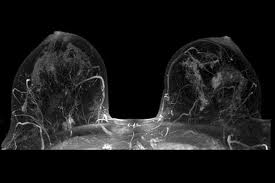

Diagnosis of lobular breast cancer is not usually made with the use of a mammogram, especially when it is still in the early stages. A breast ultrasound is usually more effective in detecting any abnormal growths in your breast. A much clearer view of the anomaly may be provided by an MRI. A breast MRI will be able to provide your doctor the location and size of the growth. A biopsy could also be obtained by getting a sample of the tissue growth and giving it to a pathologist to have it examined.